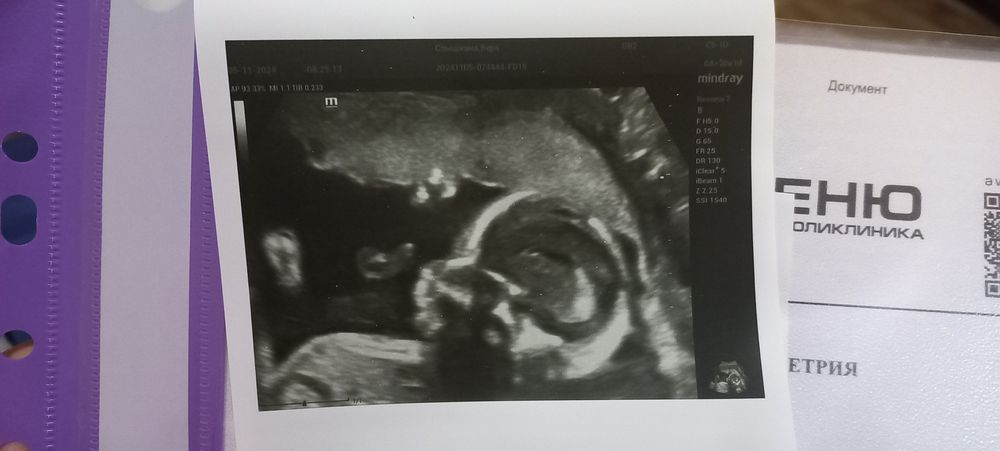

Результаты 2го скрининга!

Всё о нашей беременностиСегодня была на 2-м скрининге, на сроке 19,6)

Шейка 37, прошлое измерение на 17 неделе 35). С малышом всё хорошо, растёт наш кроха 345 грамм.

Есть предлежание плаценты, но узист успокоил, сказал, что часто до 3 скрининга поднимается и мне достаточно, чтобы на 2-4 см поднялась.